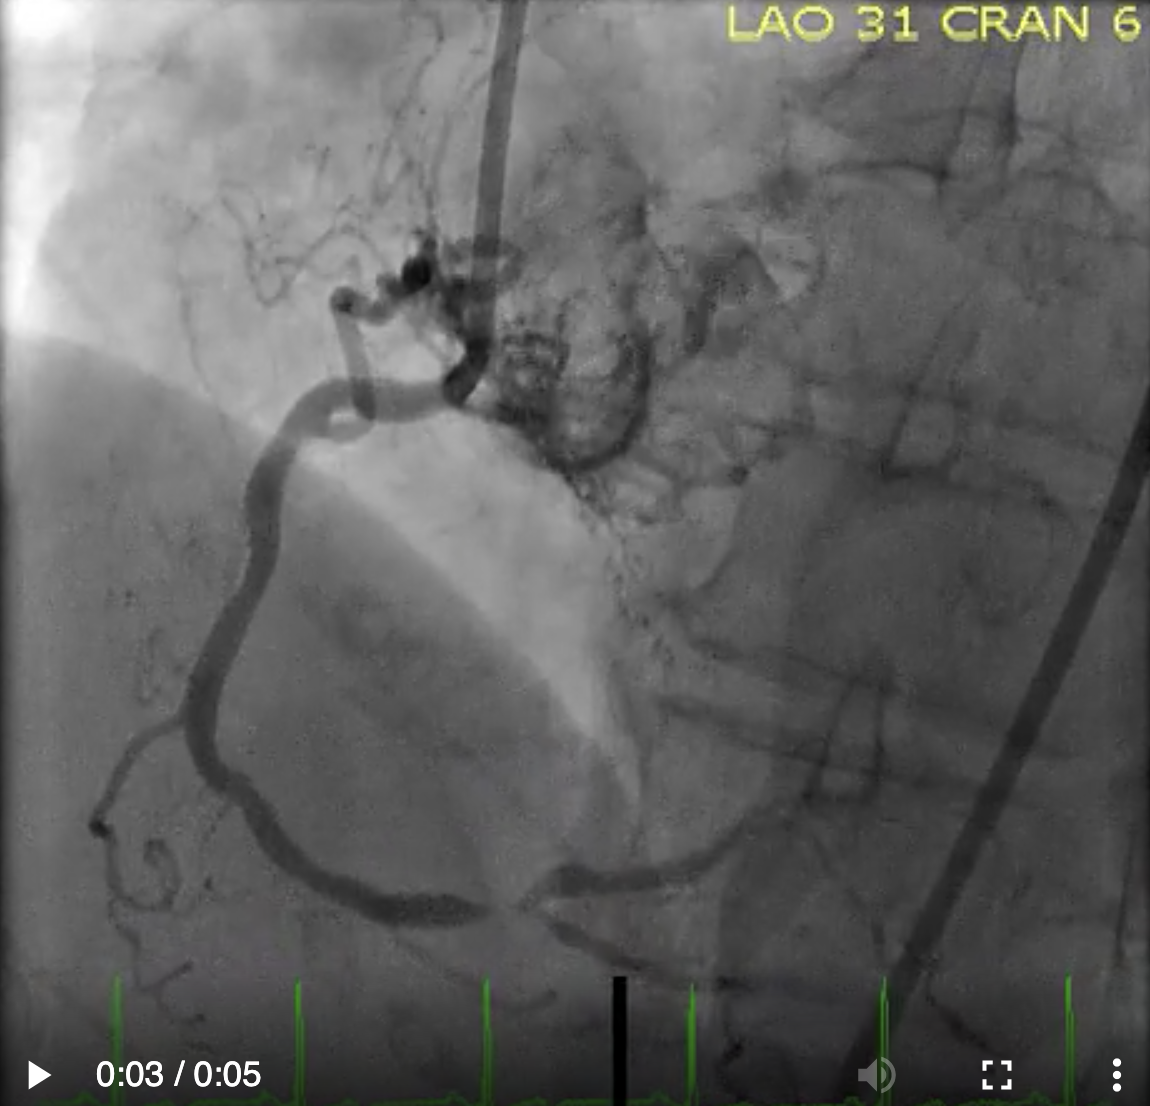

Describe the findings: